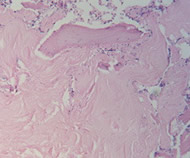

二、骨髓象:

骨髓三、骨髓鐵染色。